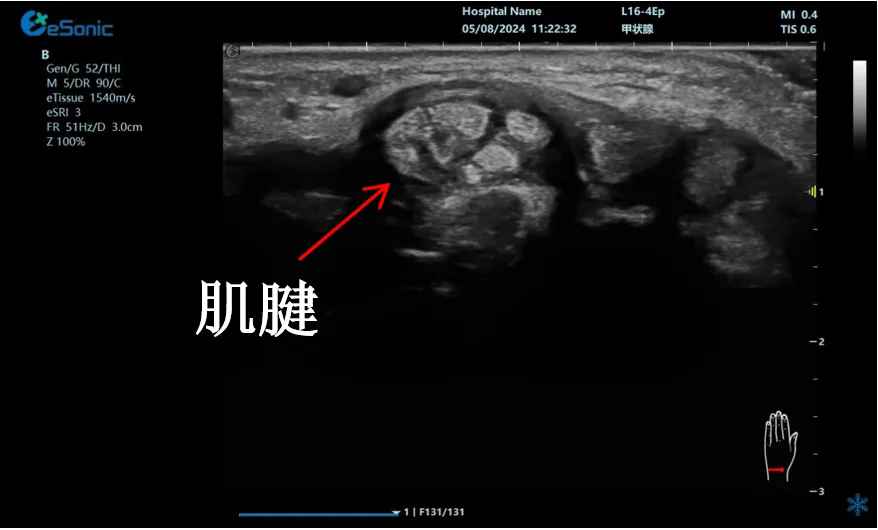

穿刺针智能MAP技术在钙化性肌腱炎的应用

【背景】:冈上肌腱内见强回声钙化灶(见标识箭头)

【治疗】:穿刺捣碎钙化灶,并抽吸;注射药物,消炎止痛。

【痛点】:普通穿刺增强,不能有效区分同为强回声的针尖和钙化灶,医生凭借经验穿刺到钙化灶。

【方案】:穿刺针智能MAP技术,采用智能彩色叠加,避免针与钙化灶混叠而难以区分,帮助引导针尖  精准到达并抽吸钙化灶。